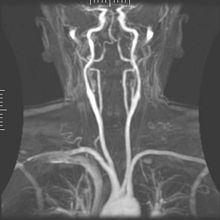

Magnetic resonance angiography (MRA) generates pictures of the arteries to evaluate them for stenosis (abnormal narrowing) or aneurysms (vessel wall dilatations, at risk of rupture). MRA is often used to evaluate the arteries of the neck and brain, the thoracic and abdominal aorta, the renal arteries, and the legs (called a "run-off"). A variety of techniques can be used to generate the pictures, such as administration of a paramagnetic contrast agent (gadolinium) or using a technique known as "flow-related enhancement" (e.g., 2D and 3D time-of-flight sequences), where most of the signal on an image is due to blood that recently moved into that plane (see also FLASH MRI).[39]

Techniques involving phase accumulation (known as phase contrast angiography) can also be used to generate flow velocity maps easily and accurately. Magnetic resonance venography (MRV) is a similar procedure that is used to image veins. In this method, the tissue is now excited inferiorly, while the signal is gathered in the plane immediately superior to the excitation plane—thus imaging the venous blood that recently moved from the excited plane.[40]